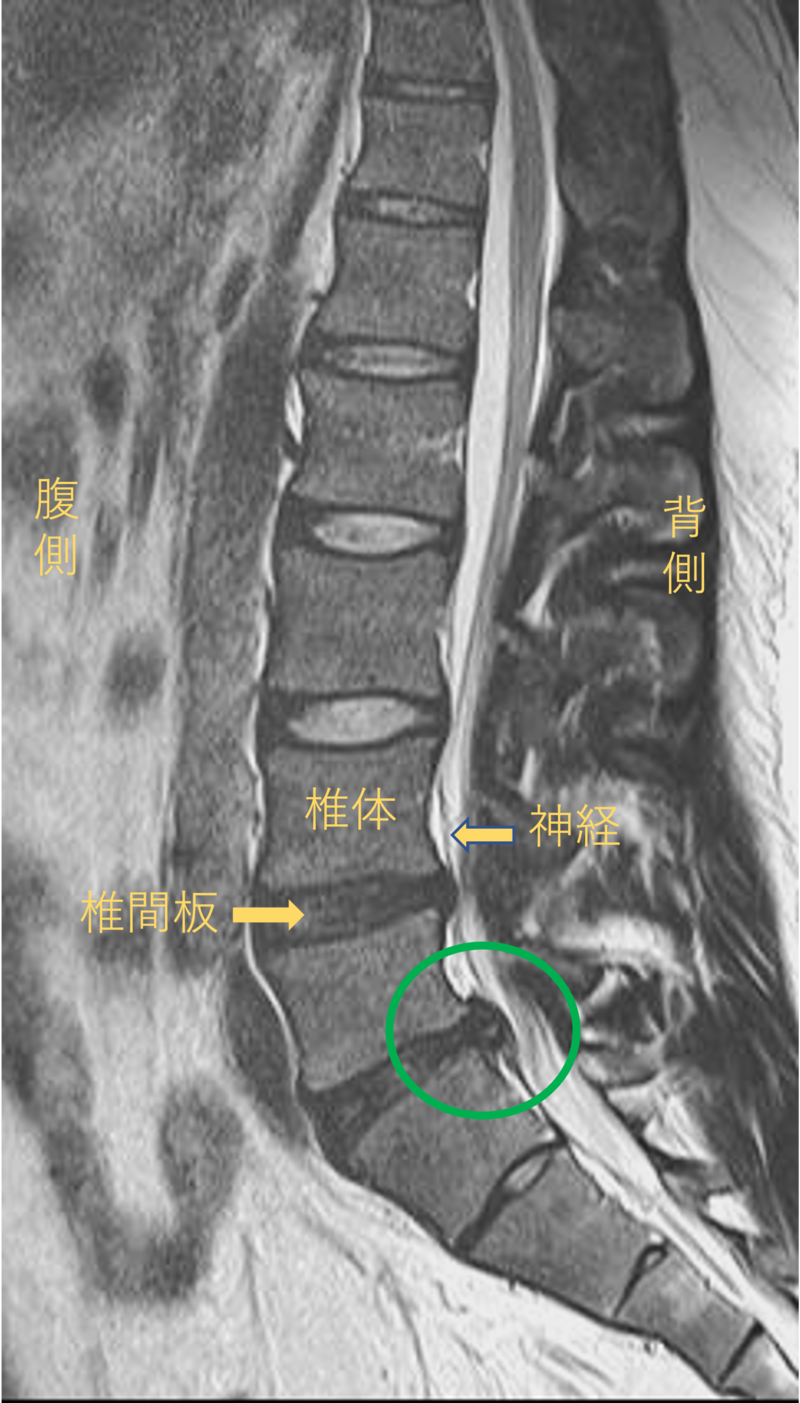

腰を横から見たMRI画像です。

腰椎という骨と骨の間に椎間板と呼ばれるクッションがあります。

このクッションの中身が飛び出す状態が椎間板ヘルニアと呼ばれます。

このMRI画像では、椎間板が背中側に飛び出して足に向かう神経が圧迫されることが痛み、しびれの原因となっておりました。